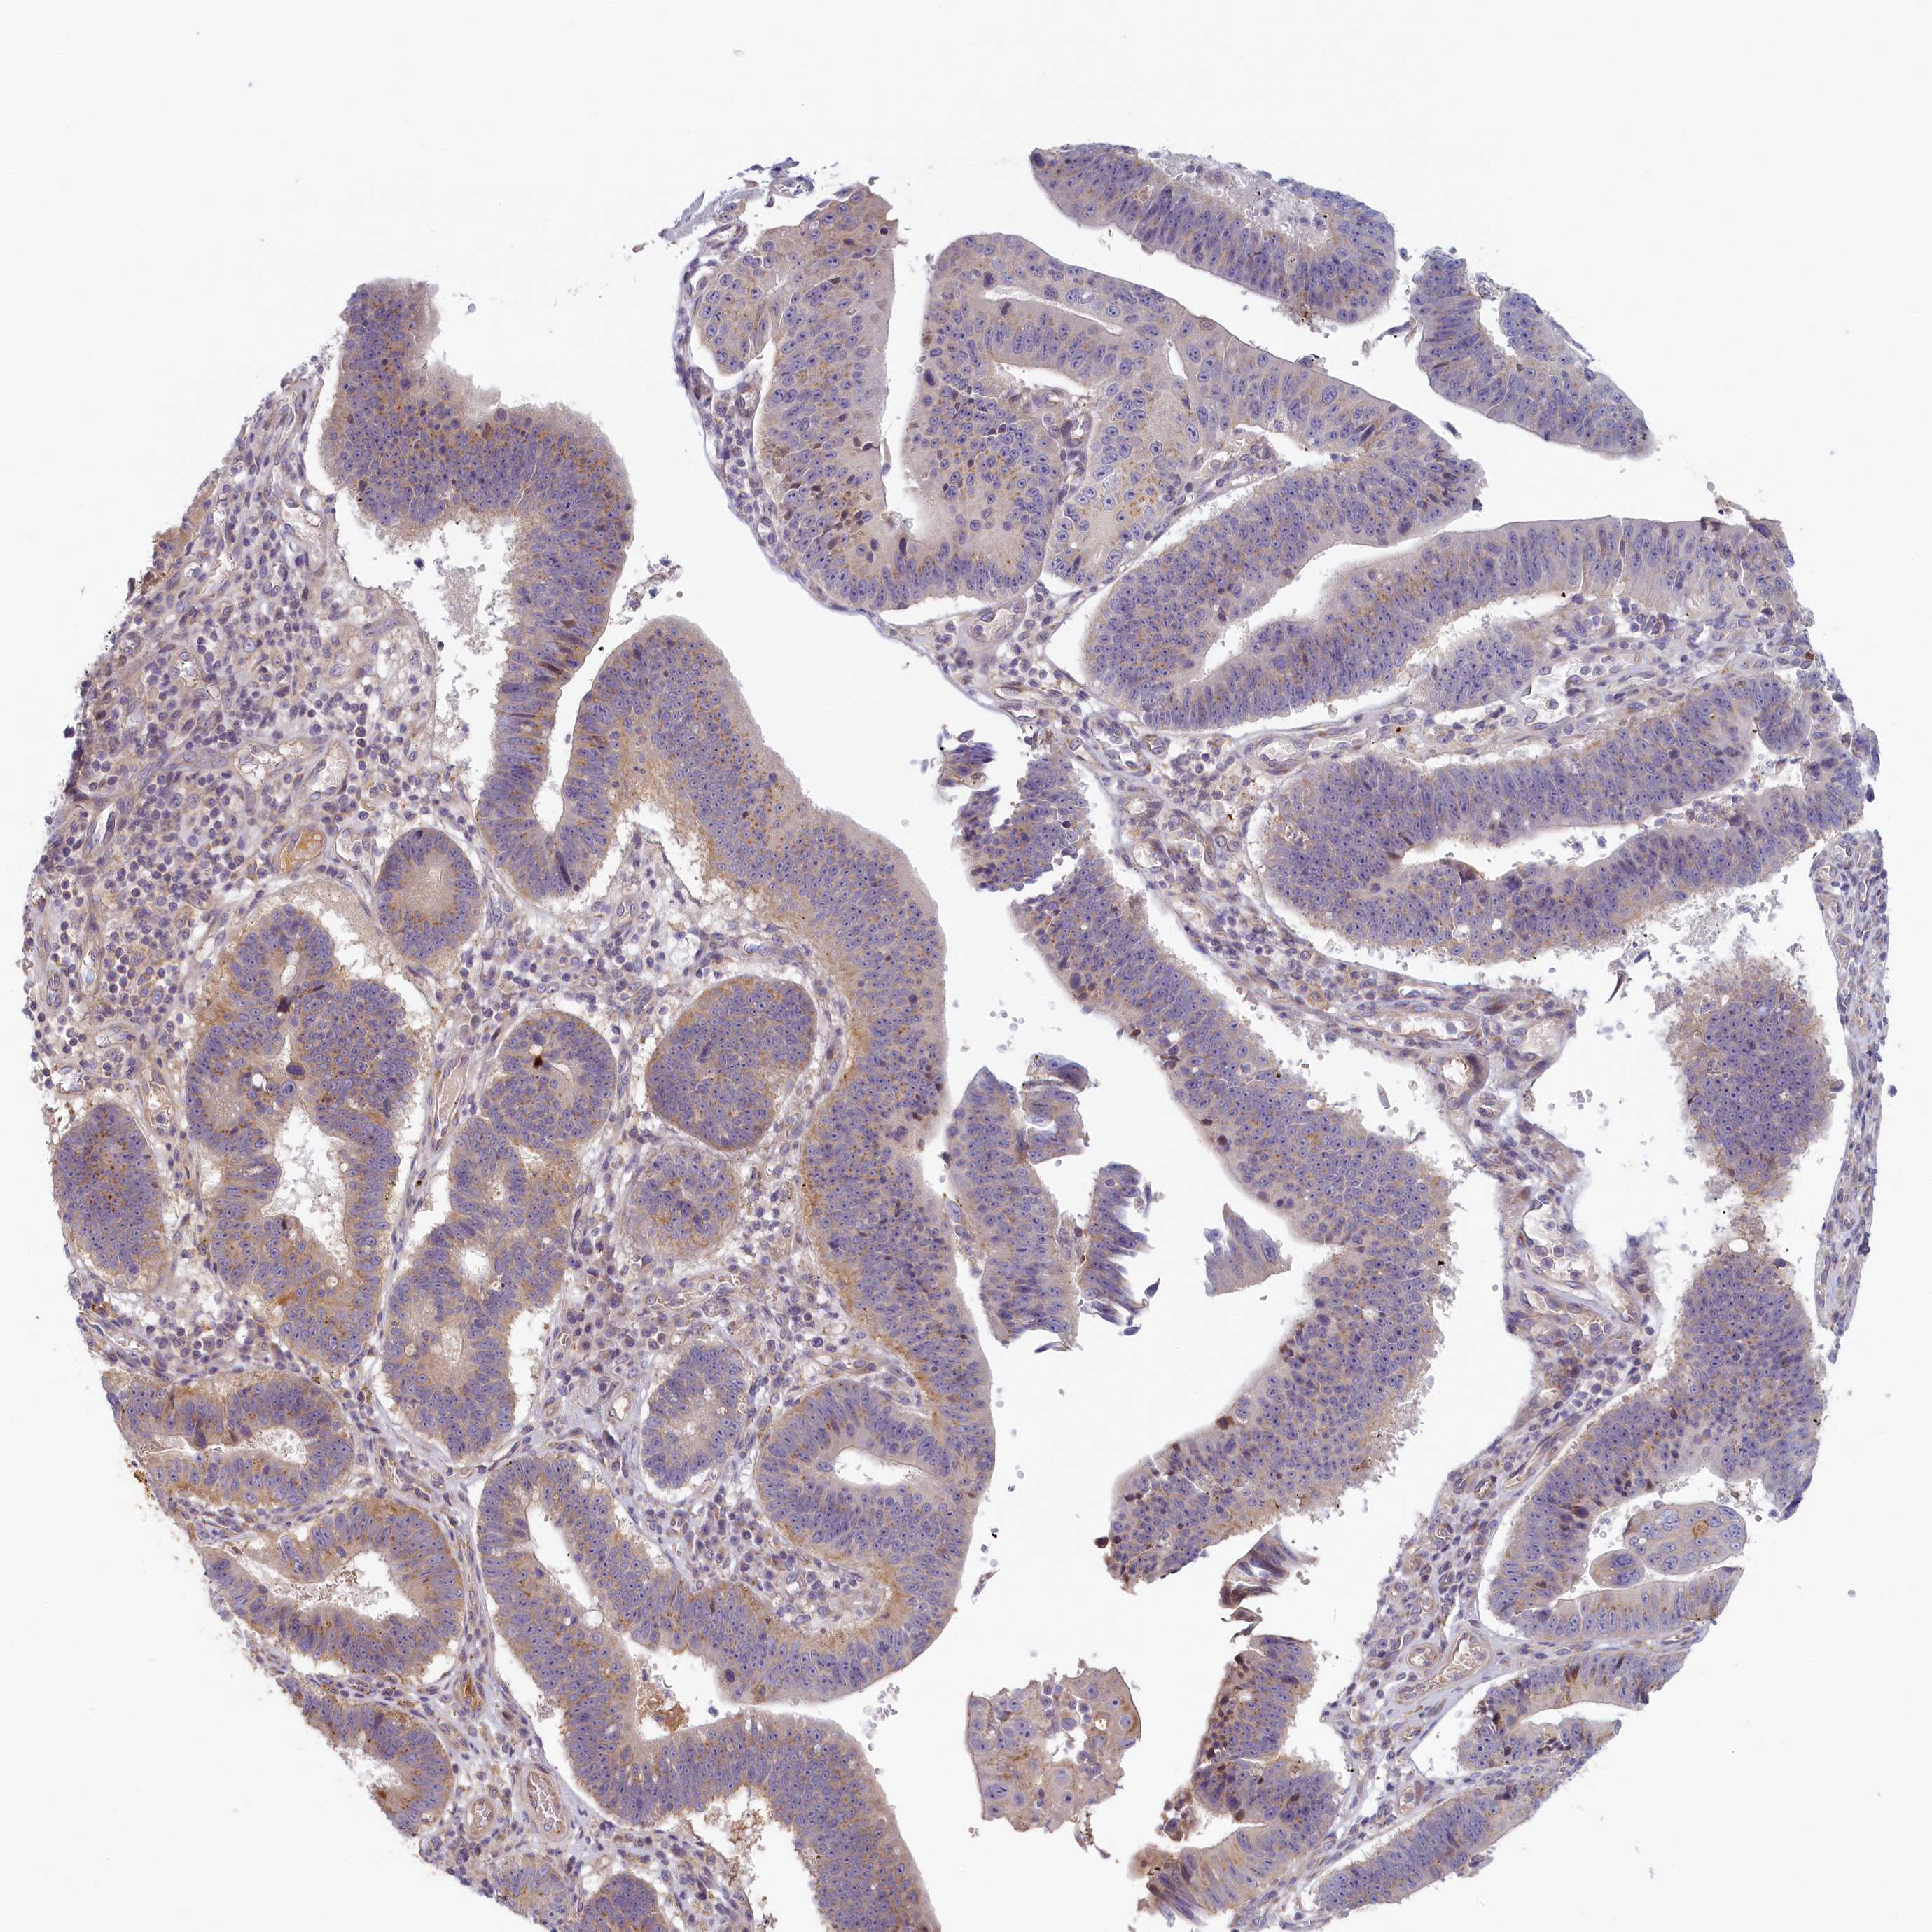

STOMACH CANCER - Protein expressioni

A mouse-over function shows sample information and annotation data. Click on an image to view it in a full screen mode. Samples can be filtered based on level of antibody staining by selecting one or several of the following categories: high, medium, low and not detected. The assay and annotation is described here.

Note that samples used for immunohistochemistry by the Human Protein Atlas do not correspond to samples in the TCGA dataset.

Antibody stainingi

Antibody staining in the annotated cell types in the current human tissue is reported as not detected, low, medium, or high, based on conventional immunohistochemistry profiling in selected tissues. This score is based on the combination of the staining intensity and fraction of stained cells.

Each image is clickable and will lead to virtual microscopy that enables deeper exploration of all samples and also displays staining intensity scores, fraction scores and subcellular localization as well as patient and tissue information for each sample.

Antibody HPA041019

Antibody HPA042033

Staining

High

Medium

Low

Not detected

Intensity

Strong

Moderate

Weak

Negative

Quantity

>75%

75%-25%

<25%

None

Location

Nuclear

Cytoplasmic/membranous

Cytoplasmic/membranous,nuclear

Adenocarcinoma, NOS